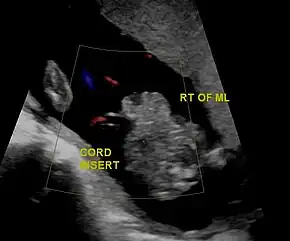

Gastrochisis in ultrasound: defect is right to midline

In the developed world, around 90% of cases are identified during normal ultrasound screens, usually in the second trimester.[17]